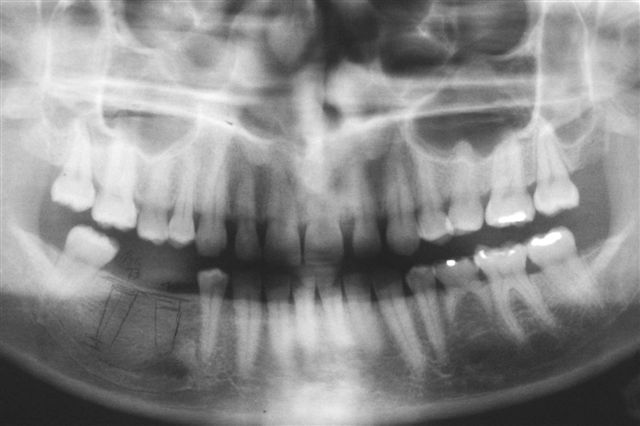

Ukázka zákroku implantace